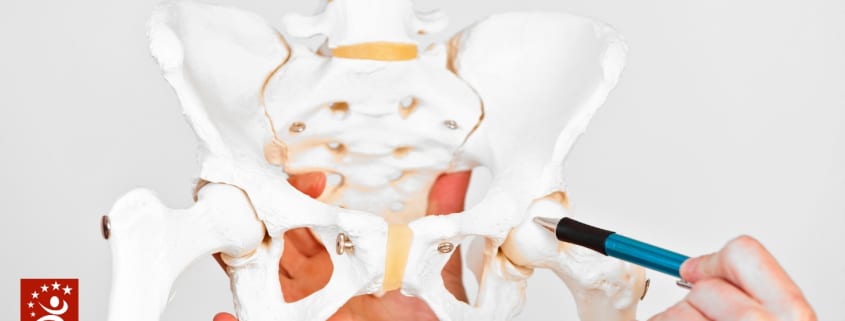

ABOUT THE HIP

The hip joint is one of the largest joints in the body. The hip joint is a connection point between the legs and torso. It is a ball-and-socket joint. The socket is formed by the acetabulum, which is part of the large pelvis bone. The ball is the femoral head, which is the upper end of the femur (thighbone). This type of joint offers a wide range of motion and provides support for the legs to hold the body. The function of the hip joint is to provide balance and support for the upper body, move the upper leg, and hold one’s body weight. The ball and socket joint lets the upper leg move at 3 degrees to allow for the following movements:

Each hip bone is made up of three bones. It may look like one bone, but each hip bone is made up of the ilium, pubis, and ischium, which are completely fused.